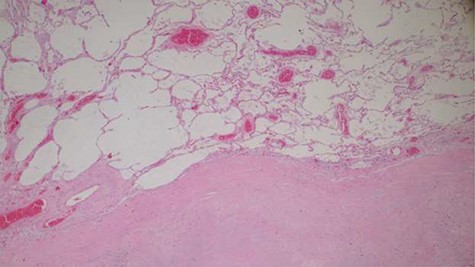

Histopathology analysis of the lung specimens revealed mixed chronic inflammatory infiltrates associated with pulmonary vascular thrombosis and areas of extensive necrosis (Figs 3 and 4). Bowel tissue sections revealed severe ischemic necrosis and mesenteric vessel thrombosis (Fig. 5). Thus, the primary causes of death were ruled to be ischemic colitis and pulmonary thrombosis due to COVID-19. The underlying disease conditions contributing to the cause of death being hypertensive heart disease, diabetes mellitus and septicemia.

Histopathology of the bowel tissue showing ischemic necrosis and the vascular thrombosis (hematoxylin and eosin ×100).